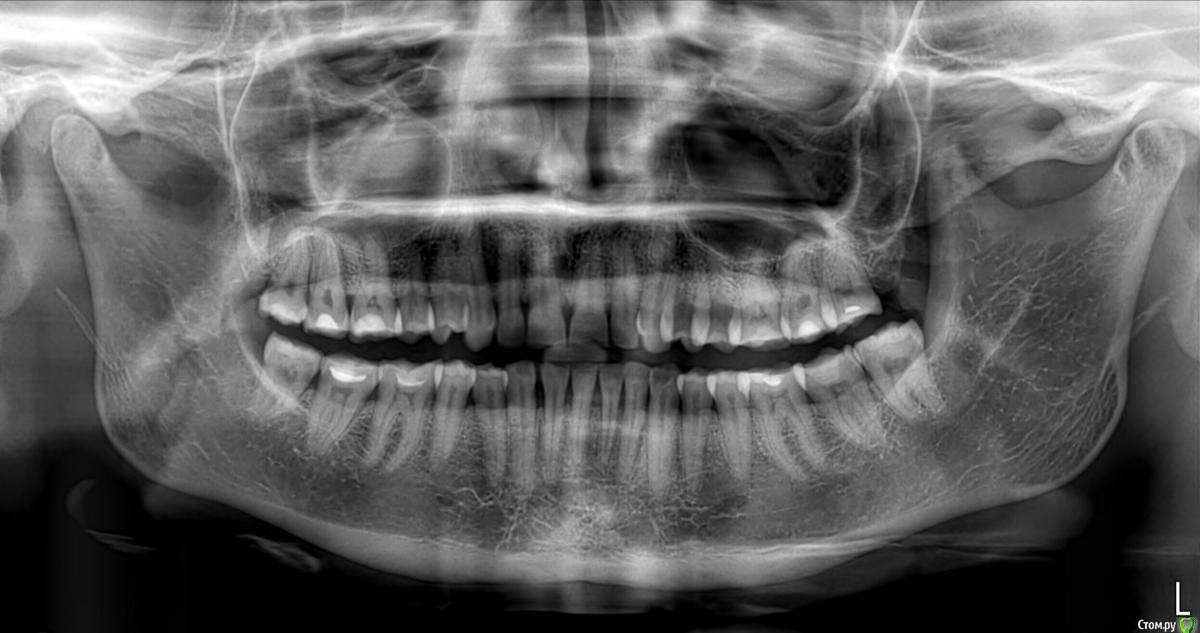

Ольга2000 Опубликовано 27 октября, 2019 Поделиться Опубликовано 27 октября, 2019 Здравствуйте. Мне 37 лет, ничего не беспокоит, нет повышенной чувствительности, кровоточивости. Мне кажется, что такие зубы у меня были последних лет 10, т.е. каких то изменений я не замечала.Делая последний раз гигиену ротовой полости врач сказала, что ей не нравится мой прикус. Через некоторое время я открывала зубами лекарство (понимаю, что так нельзя) и откололся кусочек переднего зуба. Это и подтолкнуло к записи к врачу.Первый врач осмотрел, сделал фотографии и сказал, что надо поднимать прикус с помощью пломб, пломбировать оголённые шейки зубов и ещё на отбеливание записал.Вчера была на приёме у ортодонта. Сделал снимок, сказал что с прикусом ничего не надо делать, посоветовал проконсультироваться с пародонтологом, т.к. поднимается кость. Я не знаю что мне делать. У меня следующие вопросы: 1. Надо ли поднимать прикус?2. Надо ли пломбировать оголение шеек зубов?3. На 11 и 21 зубах бороздки. Что с ними делать?4. Может капу на ночь сделать, чтобы зубы не стирались?5.И вообще что мне надо делать в обязательном порядке? И в необязательном тоже. Спасибо за ответы. Ссылка на комментарий

krokomot Опубликовано 27 октября, 2019 Поделиться Опубликовано 27 октября, 2019 По вашим фотографиям не возможно сказать нужно ли вам поднимать прикус, скорее всего да, слевой стороны у вас стираемость зубов, зубы попадают бугор на бугор, есть смещение центральной линии. также с левой стороны 6й зуб визуально не в очень хорошем состоянии. нужно ли вам что то делать? вы должны решить сами, зубы слева на буграх сточены до дентина, то есть эмаль уже полностью стерта далее с течением времени зубы начнут изнашиваться всё быстрее и быстрее. наличие полосок на нижних зубах можно не пломбировать, а скорректировать чистку зубов перейдя на выметающие движения , а не горизонтальные. если вы хотите еще 37 лет прожит со своими собственными зубами и не испытывать проблем, то нужно пройти ортодонтическое лечение и восстановить анатомию стертых зубов керамикой. Это остановит стираемость, а можете это сделать через 10 лет, но объем вмешательства возрастет кратно... 1 Ссылка на комментарий